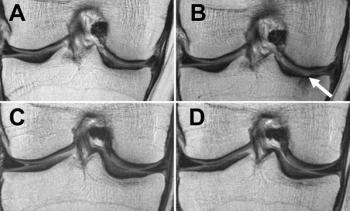

Effect of diet, exercise on people who are overweight or obese who lose weight to help decrease knee cartilage deterioration.